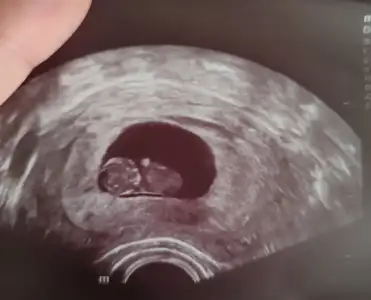

Gittim canım. Ben de size yazacaktım ilaçların son durumunu. Bebiş çok şükür iyi, tosbalak olmuş baya 😍 yan yatıyordu, soldaki başı, sağdaki gövdesi 😍 doktor bir hafta daha fitili sadece akşamladı kullan ve bırak dedi. 12. Haftada fetal DNA testi istediğimi söyledim. 12. Haftaya koydu bir dahaki muayeneyi. Sanırım o hafta fetal DNA testimiz de olur.

Ama tosbalağıma bakın kızlar kocaman olmuş 9+3 olmuşuz. Uygulamayla aynı gidiyor. 26mm. aydodo aydodo yarın da senden güzel haberi bekliyoruz 😍